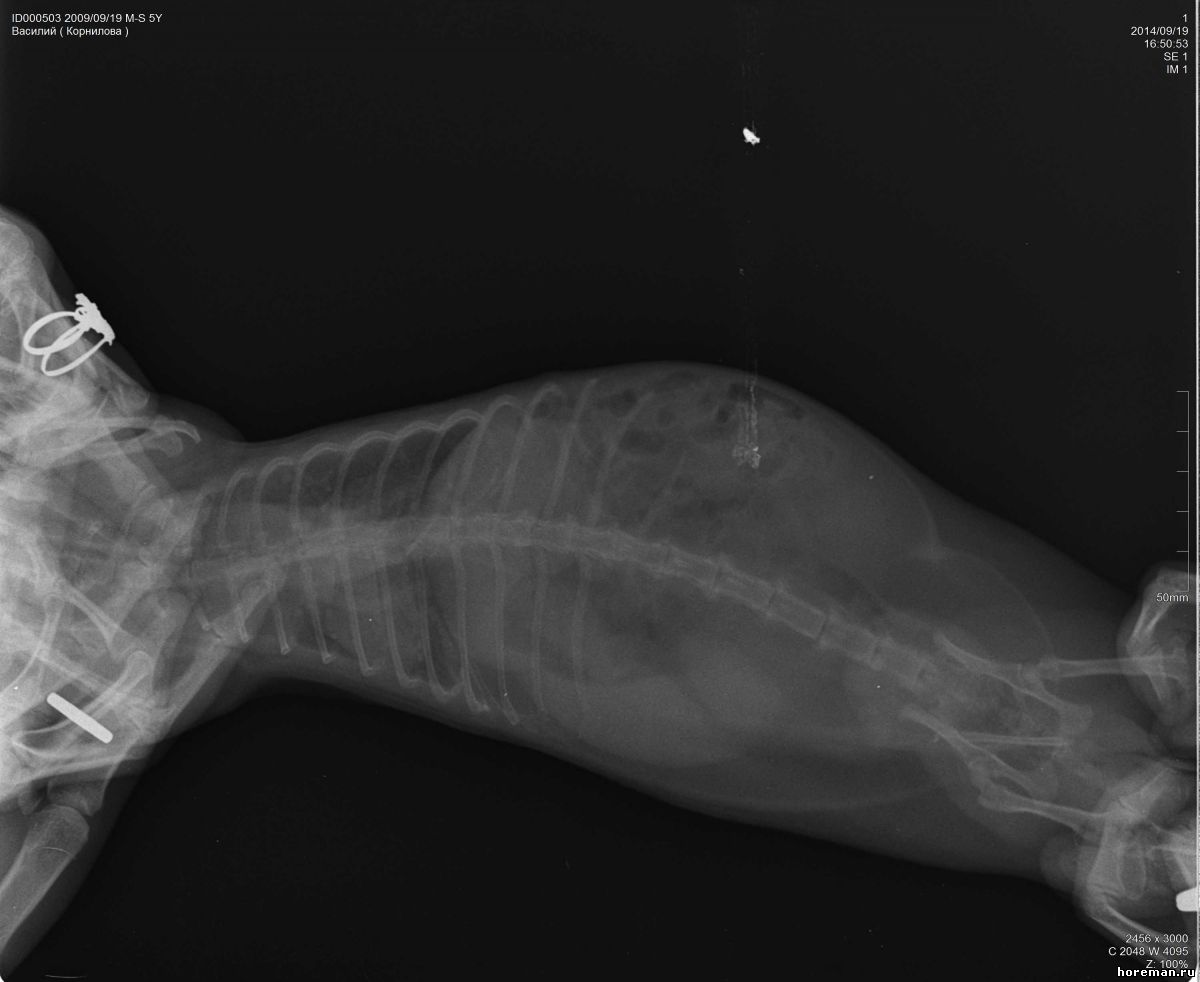

Добрый день! Нужно Ваше мнение по снимкам позвоночника моего хорька. 5 лет, кастрирован. Проблема с позвоночником, ползает на задних лапах, болевых ощущений нет, так же энергичен, игрив. Анализы все хорошие. Снимки не очень хорошего качества, завтра переделаем, но все же....

Подскажите.....Мнения нашего вета это защимление нервов в грудном отделе и что то там с позвонком выше поясницы, говорит нужна операция нейрохирургическая... :'(

Прикрепленный файл: 1991322.jpg (51.9 Kb) · 0357150.jpg (62.6 Kb) · 7876473.jpg (55.9 Kb)